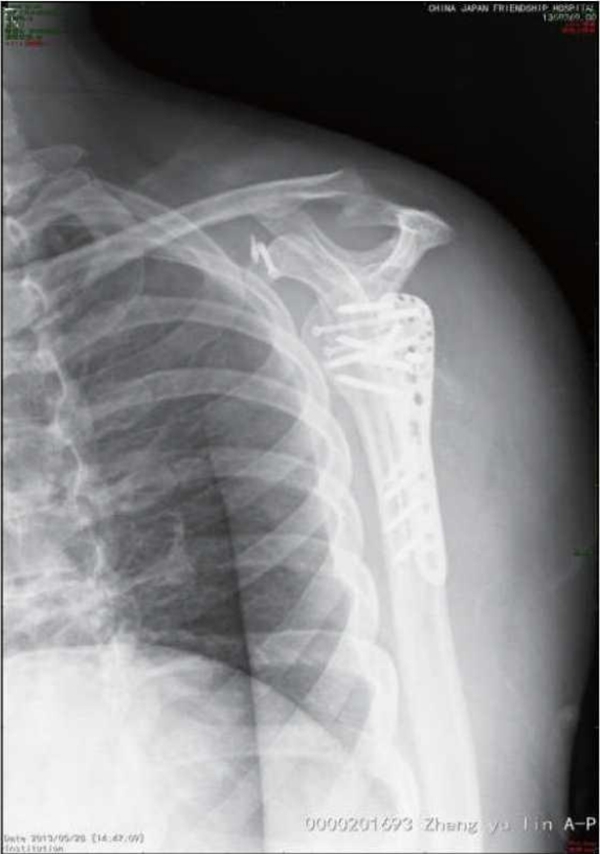

肱骨近端骨折内固定术后整体并发症发生率为30%。其中,常见的并发症主要有螺钉切出/穿透关节面、肱骨头内翻畸形、肱骨头缺血坏死、髓内钉移位、骨折不愈合、内固定断裂等(图1~3)。

图1 骨近端骨折术后不愈合、肱骨头内翻

图2 肱骨近端骨折术后肱骨头缺血性坏死、骨吸收